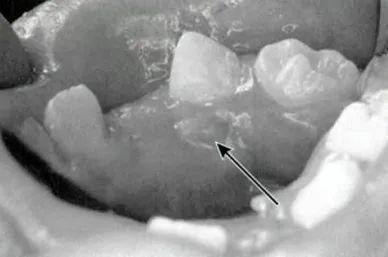

龋齿导致的根尖周脓肿

先看看下面这张图,是不是有点明白为啥要钻开牙齿做根管治疗了?

很多孩子牙髓感染,和“甜蜜的童年”有关。孩子上幼儿园后,各种零食、糖果打开了新世界的大门,也悄悄地满足了“小蛀虫”在牙齿上作祟的条件。

牙髓感染后,引起的炎症便能够一路蔓延,引起上图的恶果。

当然,除了蛀牙,磕伤牙齿也可能引起这样的脓包。这个年龄段的小朋友活泼好动,一不小心把门牙磕伤后,也容易造成牙根内部的牙髓坏死、发炎。

这种发炎引起的“脓包”,学名叫做根尖周脓肿。经过正规的根管治疗,它通常会很快消退(千万别上手挤!)。